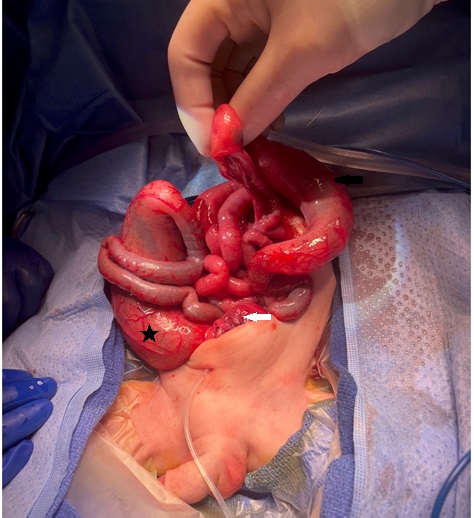

Intraoperative photo showing the dilated cecum and ascending colon (black arrow), with an abrupt change in caliber at the transverse colon. Pouch colon (black asterisk) and urinary bladder (white arrow) are also visible.

Tables